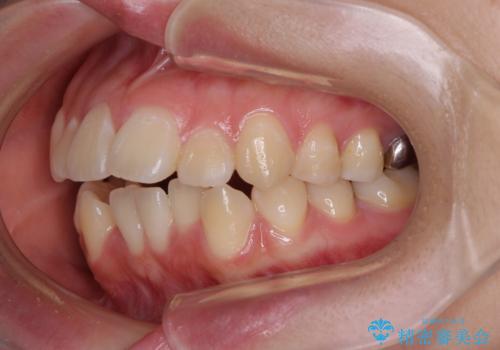

- 下の前歯のデコボコと、口元の突出感を改善したいと来院された患者様です。

突出感の強い上顎前歯をしっかりと後方移動させるため、上顎の裏側の補助装置(リンガルアーチ)とアンカースクリューを併用しています。

上下左右の第一小臼歯を抜歯して、目立ちにくいワイヤー装置で矯正を行いました。